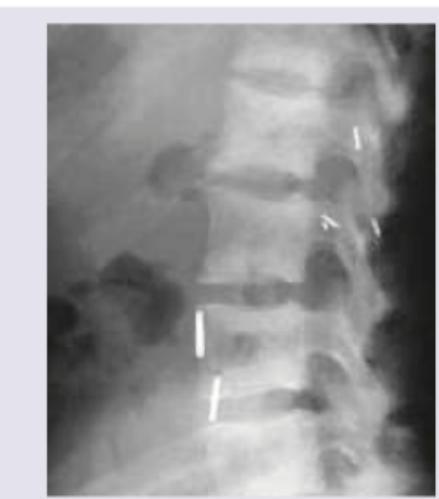

Explanation: ***Osteitis fibrosa cystica*** - The combination of **elevated calcium**, **decreased phosphate**, and **elevated alkaline phosphatase** is classic for **primary hyperparathyroidism**, which leads to osteitis fibrosa cystica. - The X-ray image shows evidence of **bone resorption**, particularly **subperiosteal resorption** in the distal phalanges, which is highly characteristic of this condition. *Paget's disease of the bone* - Characterized by **disordered bone remodeling**, leading to localized areas of **bone enlargement** and **sclerosis**, often with a normal calcium and phosphate level. - The elevated alkaline phosphatase is consistent, but normal calcium and phosphate would be expected, and the X-ray findings for Paget's usually show pronounced **cortical thickening** or a **"cotton wool" appearance**. *Osteomalacia* - Results from **defective mineralization of bone due to vitamin D deficiency**, leading to low calcium or phosphate, and elevated alkaline phosphatase. - While laboratory findings can be similar, osteomalacia often presents with characteristic **pseudofractures (Looser zones)** on X-ray, which are not depicted here. *Osteoporosis* - Involves **decreased bone density** and increased fracture risk, typically with normal calcium, phosphate, and alkaline phosphatase levels. - The X-ray would show generalized **osteopenia**, but the specific findings of subperiosteal resorption and the given lab values (elevated calcium, decreased phosphate) point away from uncomplicated osteoporosis.